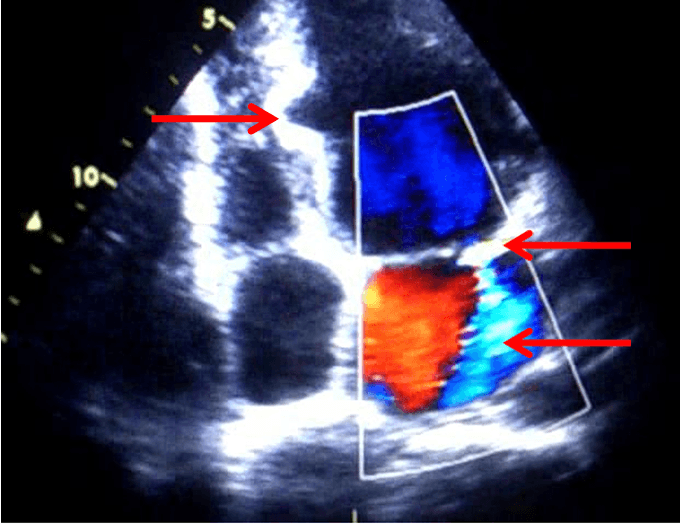

При трансторакальной эхокардиографии отмечено увеличение конечно-диастолического размера левого желудочка до 6,2 см и объёма левого предсердия до 66 мл, а также миксоматозное изменение обеих створок митрального клапана с пролапсом и регургитацией 2-й степени. Особо обращала на себя внимание выраженная неоднородность межжелудочковой перегородки с зоной локального фиброза, истончения и изменённой кинетики (акинезия, дискинезия) в средней трети (рис. 1). При компьютерной томографии сердца с контрастным усилением в 6-м и 9-м сегментах левого желудочка были визуализированы два врождённых дивертикула сердца размером 16 х 11 х 10 мм и 28 х 6 х 16 мм (рис. 2). При МРТ сердца с контрастным усилением в 6-м и 9-м сегментах левого желудочка также визуализировались врождённые дивертикулы сердца (в 6-м сегменте на всю толщину стенки левого желудочка), имевшие фиброзную стенку, с её отсроченным контрастированием. Изменения в 12-м сегменте ЛЖ были расценены как несформировавшийся дивертикул (рис. 3).